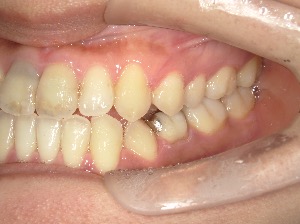

患者さんの年齢 30代 男性 症状 ガタガタを治したい 治療内容 ワイヤー矯正治療 費用 88万(税抜) 治療期間・回数 治療期間2年半、通院回数20回 メリット 口元が綺麗 デメリット・リスク 期間がかかることがある 患者さまの声 見た目が良くなった - 矯正治療

before